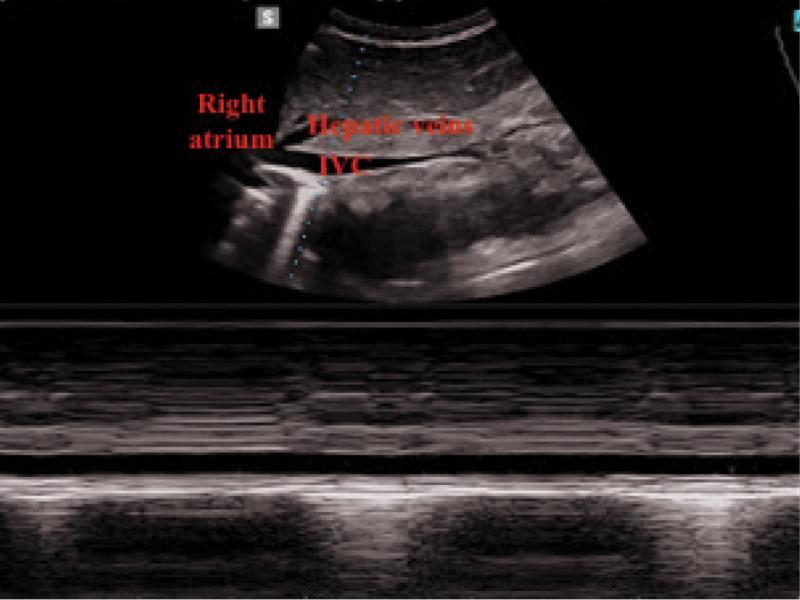

Fig. 1.